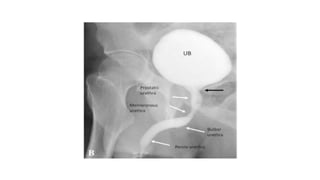

PARTS OF URETHRA

 ANTERIOR URETHRA

-PENILE URETHRA

-BULBAR URETHRA

 POSTERIOR URETHRA

- MEMBRANOUS URETHRA

- PROSTATIC URETHRA

PARTS OF URETHRA ANTERIOR URETHRA -PENILE URETHRA -BULBAR URETHRA  POSTERIOR URETHRA - MEMBRANOUS URETHRA - PROSTATIC URETHRA